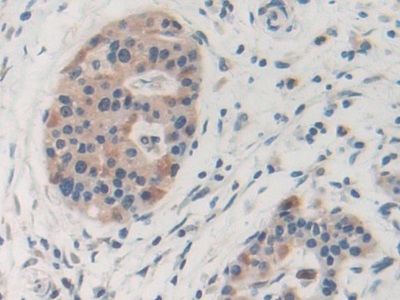

Polyclonal Antibody to Chitinase-3-like Protein 1 (CHI3L1)

Product No.: PAB463Hu01

Organism species: Homo sapiens (Human)

Monoclonal Antibody to Chitinase-3-like Protein 1 (CHI3L1)

Product No.: MAB463Hu22

Organism species: Homo sapiens (Human)